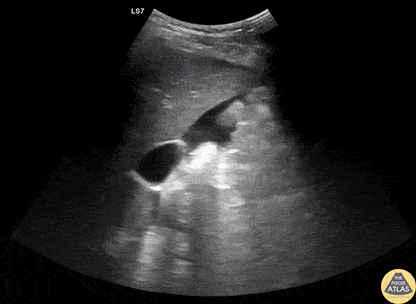

Trauma - +FAST Exam from Splenic Injury

20s M presented with abdominal and back pain several hours after a fall off a ladder, and on FAST exam, had a large amount of free fluid seen in the pelvis/lower abdomen and in the RUQ. He was slightly tachycardic but normotensive, so underwent CT of the abdomen/pelvis, which demonstrated a significant spleen injury which was managed by IR embolization. Dr. Greg Wiener, PGY3 Denver Health Residency in Emergency Medicine